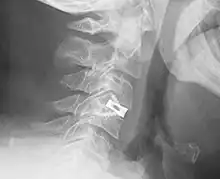

An interbody fusion cage (colloquially known as a "spine cage") is a prosthesis used in spinal fusion procedures to maintain foraminal height and decompression. They are cylindrical or square-shaped devices, and usually threaded. There are several varieties: the Harms cage, Ray cage, Pyramesh cage, InterFix cage, and lordotic LT cage, all of which are made from titanium; the Brantigan cage, made from carbon fibre; and the Cortical Bone Dowel, which is cut from allograft femur. The cages can be packed with autologous bone material in order to promote arthrodesis.[1] Such implants are inserted when the space between the spinal discs is distracted, such that the implant, when threaded, is compressed like a screw. Unthreaded implants, such as the Harms and Pyramesh cages have teeth along both surfaces that bite into the end plates.[1]